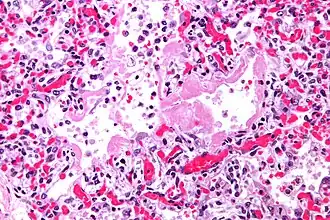

"Золотым" стандартом диагностики ОИП является биопсия легких[3].